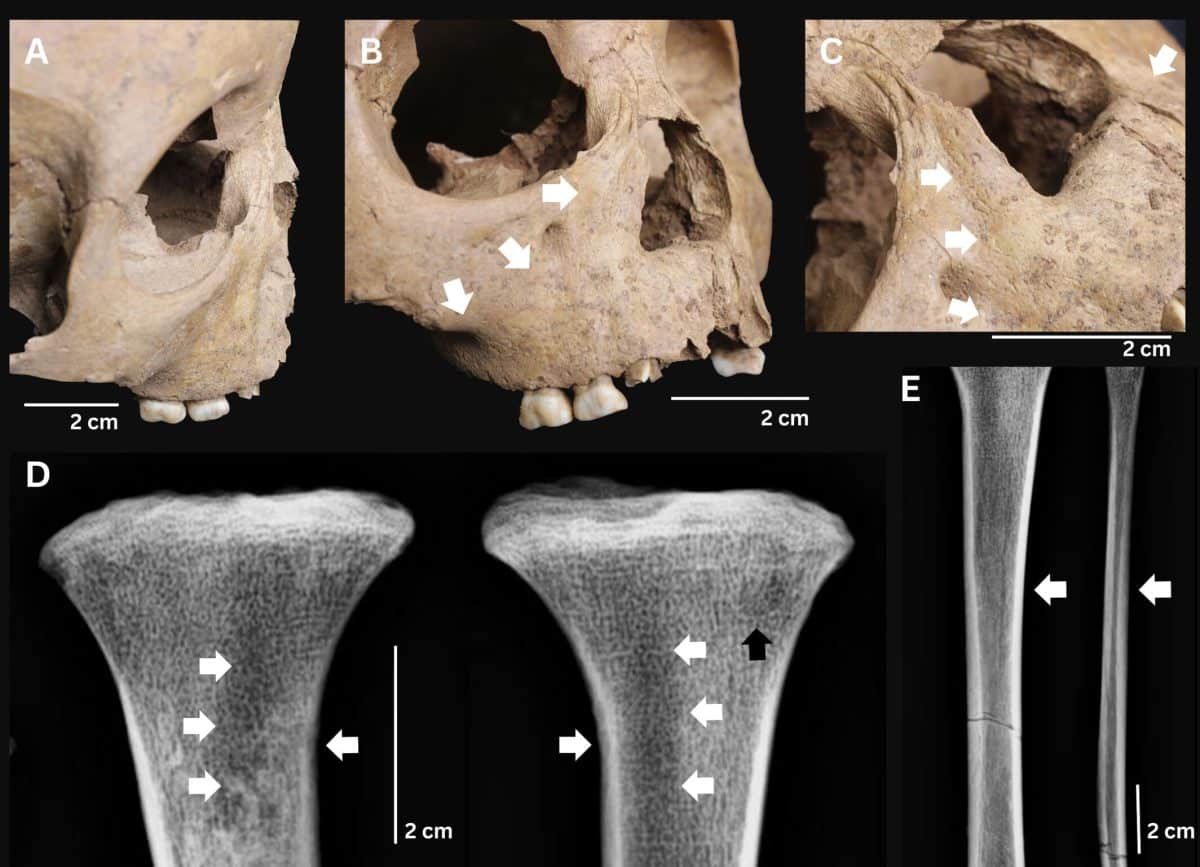

Археологи идентифицировали трех несовершеннолетних с комплексом признаков, соответствующих врожденному трепонематозу. Два случая происходят из памятника Ман-Бак на севере Вьетнама (4000-3500 лет назад), один — из памятника Ан-Сон на юге страны (3800-3200 лет назад). Наиболее показательным оказался ребенок из Ман-Бака в возрасте около 18 месяцев, у которого зафиксировали лунообразные моляры как на постоянных, так и на молочных зубах, множественные поражения костей, утолщение лобной кости и характерные узлы новообразованной костной ткани на длинных костях конечностей. Все это указало на врожденную форму.

Таким образом, авторы исследования выяснили, что врожденные формы не являются главным показателем венерического сифилиса. Картина в Ман-Баке, где поражения выявили преимущественно у детей и подростков, свидетельствует в пользу невенерической природы заболевания. В условиях тропического климата и тесного бытового контакта оно могло передаваться от матери к ребенку внутриутробно или в раннем родовом периоде.